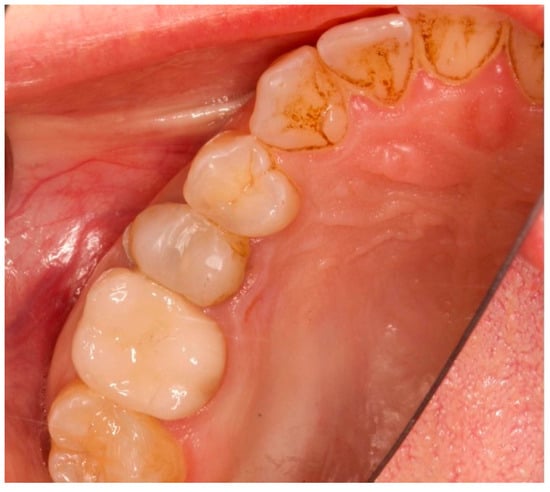

Figure 7.

Occlusal view after implant insertion at 3 months (T1).